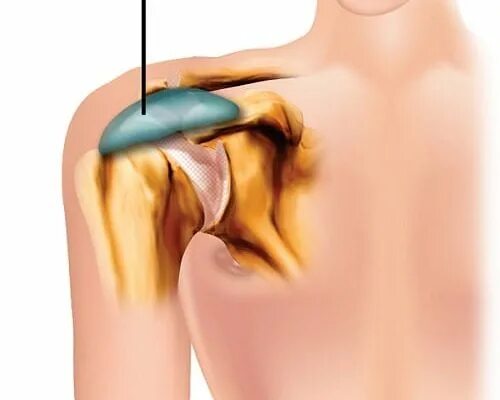

Артроз ключично акромиального сочленения плечевого